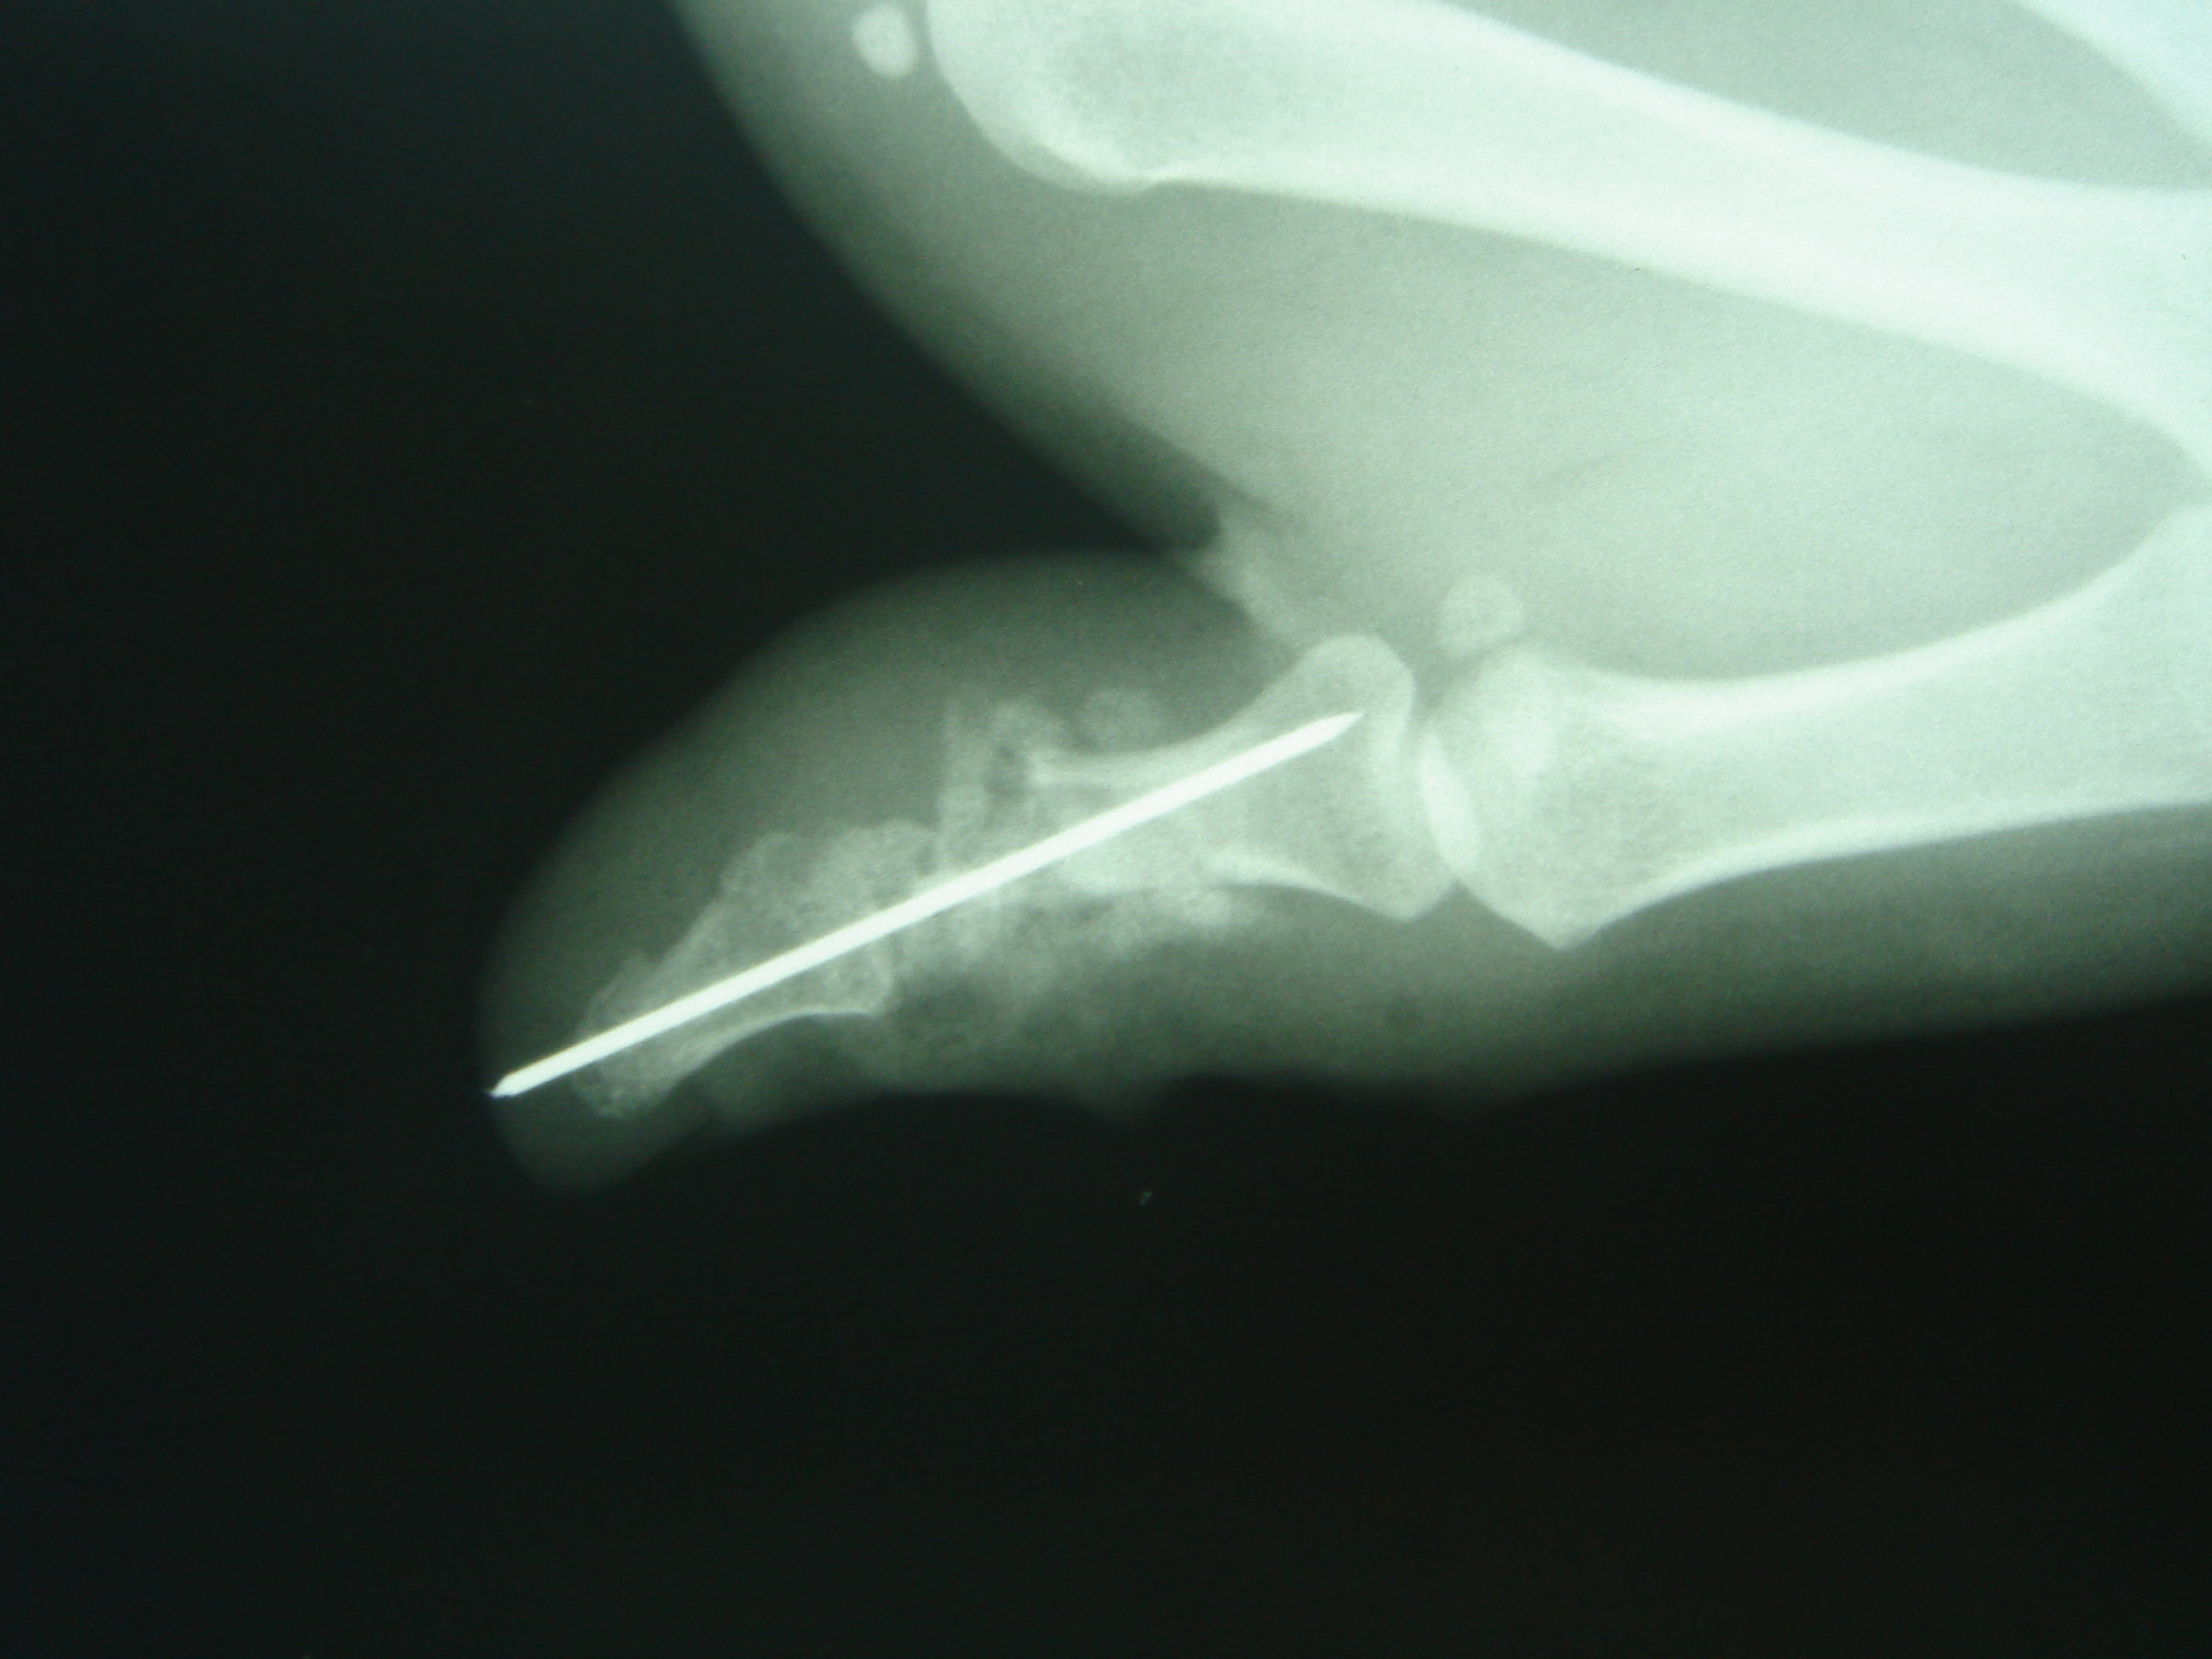

Figure 2a & 2b Immediate post operative x-rays of case 1, showing a reduced distal phalangeal joint fixed with a k-wire plus supplemented with a bone graft.

(a) Ap view. (b) Lateral view.